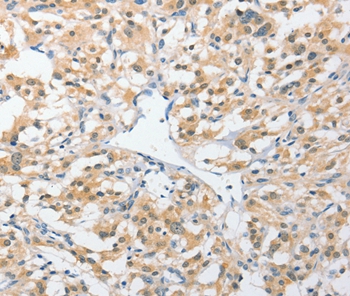

Immunohistochemical analysis of paraffin-embedded Human thyroid cancer tissue using #36168 at dilution 1/25.

Immunohistochemistry: 1:25-1:100